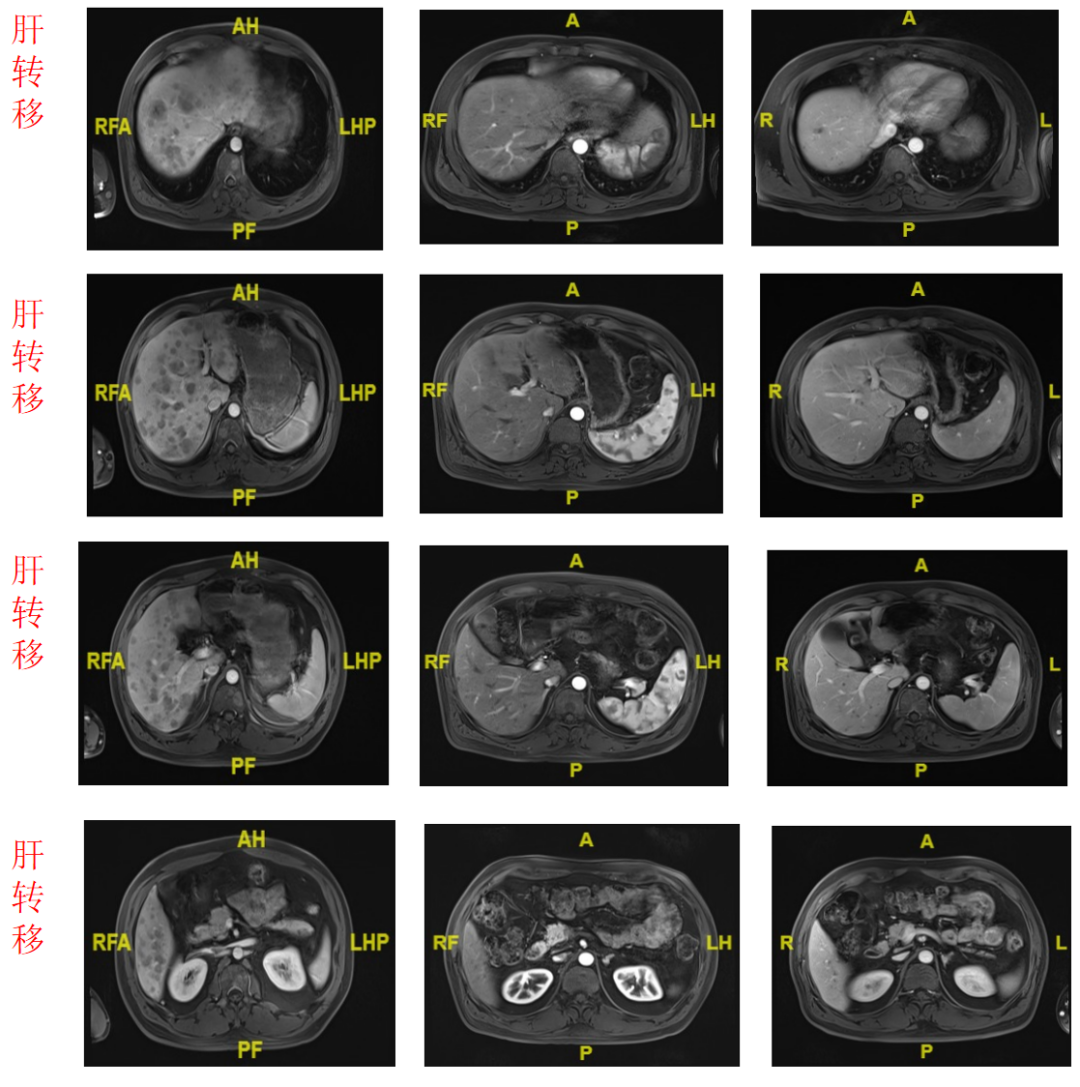

MRI(2022.7.6):肝脏表面光滑,肝脏多发T1WI低信号、T2WI略高信号结节,较前稍缩小减少,大者约17mm,增强后呈轻度强化,肝胆排泄期强化退出,肝内外胆管无扩张。胸腰椎多发转移部分稍缩小。

MRI(2022.8.19):肝脏表面光滑,肝脏多发T1WI低信号、T2WI略高信号结节,部分较前稍缩小,大者约15mm,增强后呈轻度强化,肝胆排泄期无明显摄取,肝内外胆管无扩张。胸腰椎多发异常信号灶,较前缩小。

图5.基线、C3、C4的胸、腹CT和MR影像